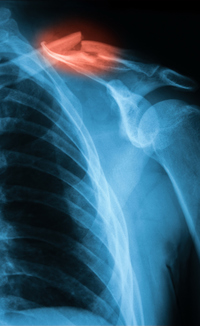

46+ Broken Shoulder Bone Healing Time Pictures

46+ Broken Shoulder Bone Healing Time Pictures. Broken shoulder recovery often includes wearing a sling to allow the broken shoulder blade to heal. Healing bone — your body knows the way.

Part of recovering from a broken shoulder is knowing what to. Healing bone — your body knows the way. While a broken shoulder may take as long as 12 weeks to heal, according to the university of buffalo sports medicine group, the advantage of doctors usually perform surgery soon after a bone fracture in the shoulder to reconstruct a healthy posture 1. This implies that the broken pieces remain near their anatomic position and treatment merely requires immobilization in a sling until occasionally the rotator cuff muscles are injured or torn at the same time as the fracture.